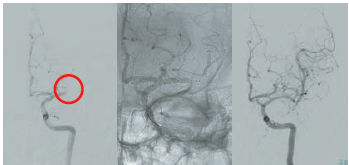

突発した神経症状(片側の顔、上下肢の運動麻痺、言葉の異常、眼球の偏位など)が脳梗塞(脳血管が詰まって発症)の場合、rt-PA静注療法の適応が拡大され、従来の“発症”後4.5時間以内に加え、“発見”4.5時間以内(例えば起床時発見例)でも、 MRI-FLAIR画像で通常発症4.5時間以降で出現する高信号を認めない場合、rt-PAを投与できます。また、発症24時間以内でearly-CT signやMRI拡散強調画像(DWI)での高信号領域(梗塞完成が示唆される領域)がある程度広範囲でも、閉塞血管をカテーテルによる血栓回収療法で再開通させると、90日後の機能予後が改善する症例が多くなることが証明されています。当センターではこれらの脳梗塞急性期再開通療法を積極的に行っています。実際の症例を紹介いたします。症例は60代男性。特に既往はありません。 仕事中に右片麻痺、運動性失語、左共同偏視が出現し倒れているところを発見され、同僚が救急要請、最終健常確認から88分で当院に搬送されました。来院後10分のCTAで左中大脳動脈の閉塞を認め(図4)、来院後26分でrt-PA静注療法開始、38分で緊急カテーテルを開始し同様の閉塞所見を確認、ステントリトリーバーを用いた血栓回収を行い、来院後55分(最終健常確認から143分)で再開通が得られています(図5)。図6が回収された血栓と回収デバイスです。術後速やかに症状は改善し、梗塞巣はわずかで済みました(図7)。入院13日後に退院され、元の仕事に復職しておられます。

図4 搬送直後のCTA

図5 閉塞していた左中脳動脈をステントリトリーバーで再通過させた